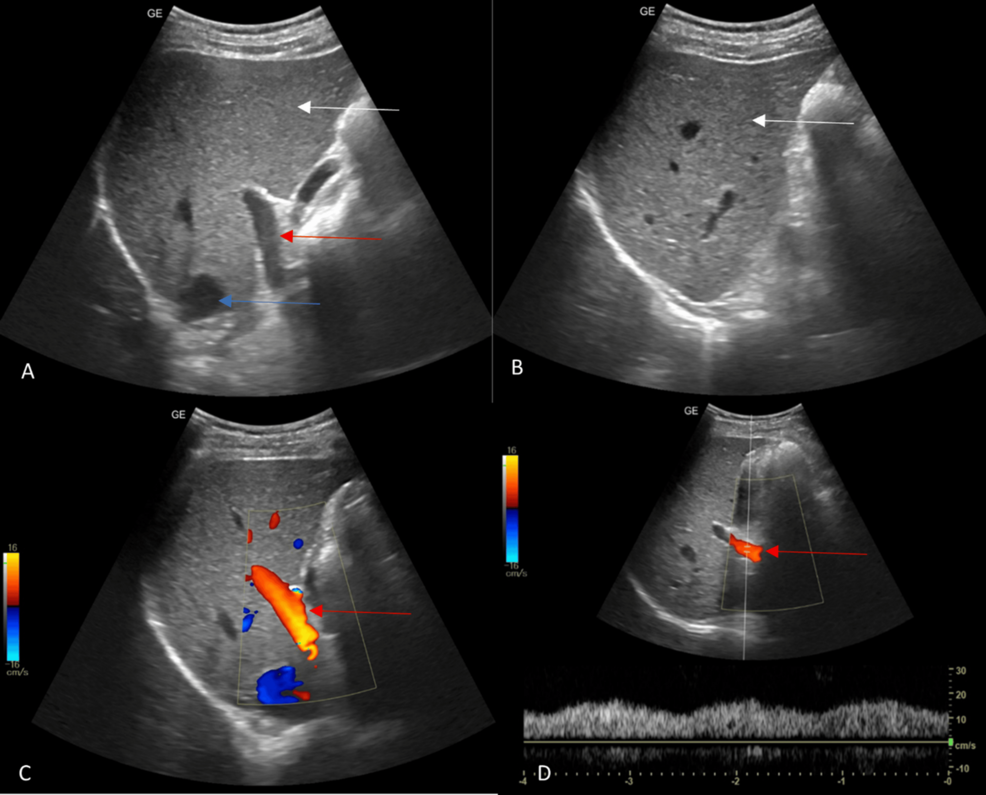

Grayscale ultrasound provides a standard anatomical image of the liver, spleen, and portal vein. Color Doppler adds a layer of functional information by displaying the direction and velocity of blood flow. This allows doctors to identify abnormalities in blood flow patterns, such as slowed flow indicating obstruction, or reversed flow suggesting the development of portosystemic collaterals. The technique can help differentiate between different types of portal hypertension – pre-sinusoidal, sinusoidal, and post-sinusoidal – each with distinct causes and management strategies.

Specifically, color Doppler ultrasound can assess parameters like the diameter of the portal vein, the velocity of blood flow within it, and the presence of blood clots (portal vein thrombosis). It can also detect associated findings like splenomegaly (enlarged spleen) and ascites (fluid buildup in the abdomen), common complications of portal hypertension. The Hepatic Vein Damping Index (DI), a measurement derived from Doppler ultrasound, can also provide insights into the severity of liver dysfunction.

Color Doppler ultrasound isn’t just useful for diagnosing portal hypertension. it also helps assess its severity and detect potential complications. The ability to identify portosystemic collaterals is particularly important, as these vessels are prone to bleeding, a life-threatening emergency. Ultrasound can also detect esophageal varices – enlarged veins in the esophagus that can rupture and bleed – with reasonable accuracy.